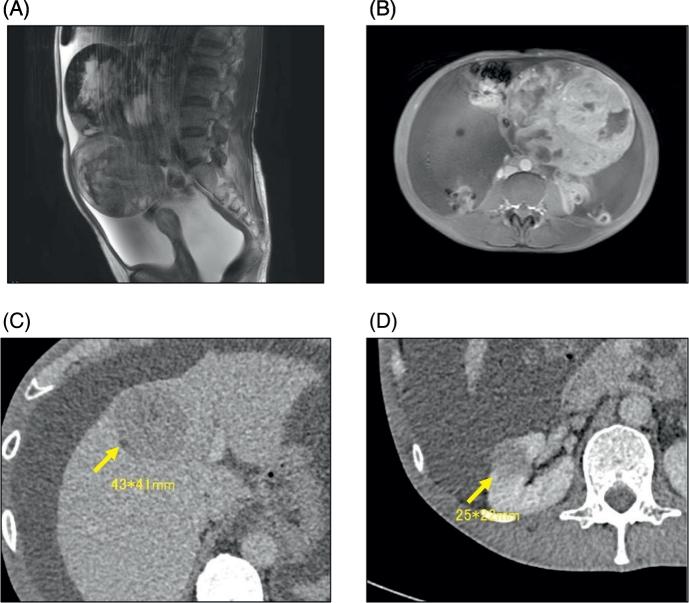

Aggressive neuroendocrine tumor of the ovary with multiple metastases treated with everolimus: A case report.

•我们描述了一名患有侵袭性原发性卵巢NET的患者,用依维莫司(一种mTOR抑制剂)成功治疗。